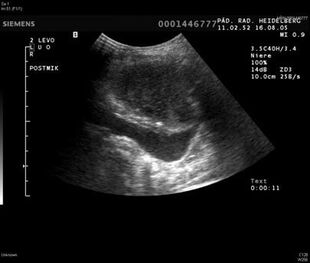

Die Nieren produzieren Urin, der aus dem Blut gereinigte Abfallprodukte, Blutsalze und Wasser enthält. Der Urin fließt dann aus den Nieren, über ein inneres Sammelsystem, dass sich zu einem...